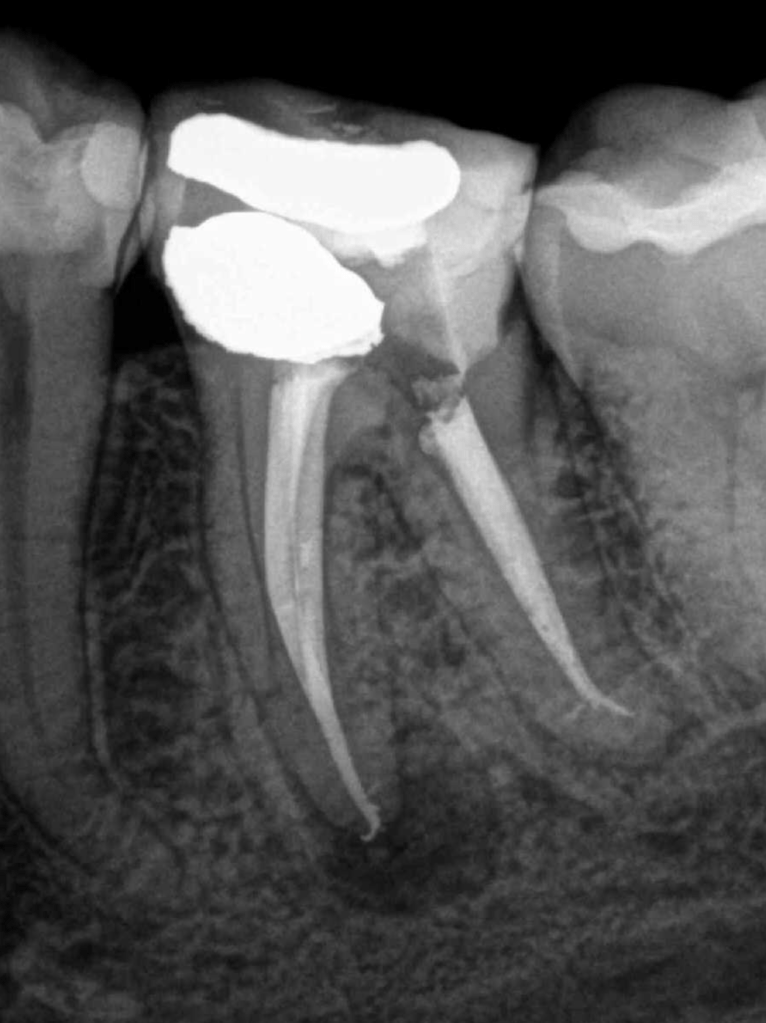

Retratamiento Molar Superior

Retratamiento Primer Molar Superior